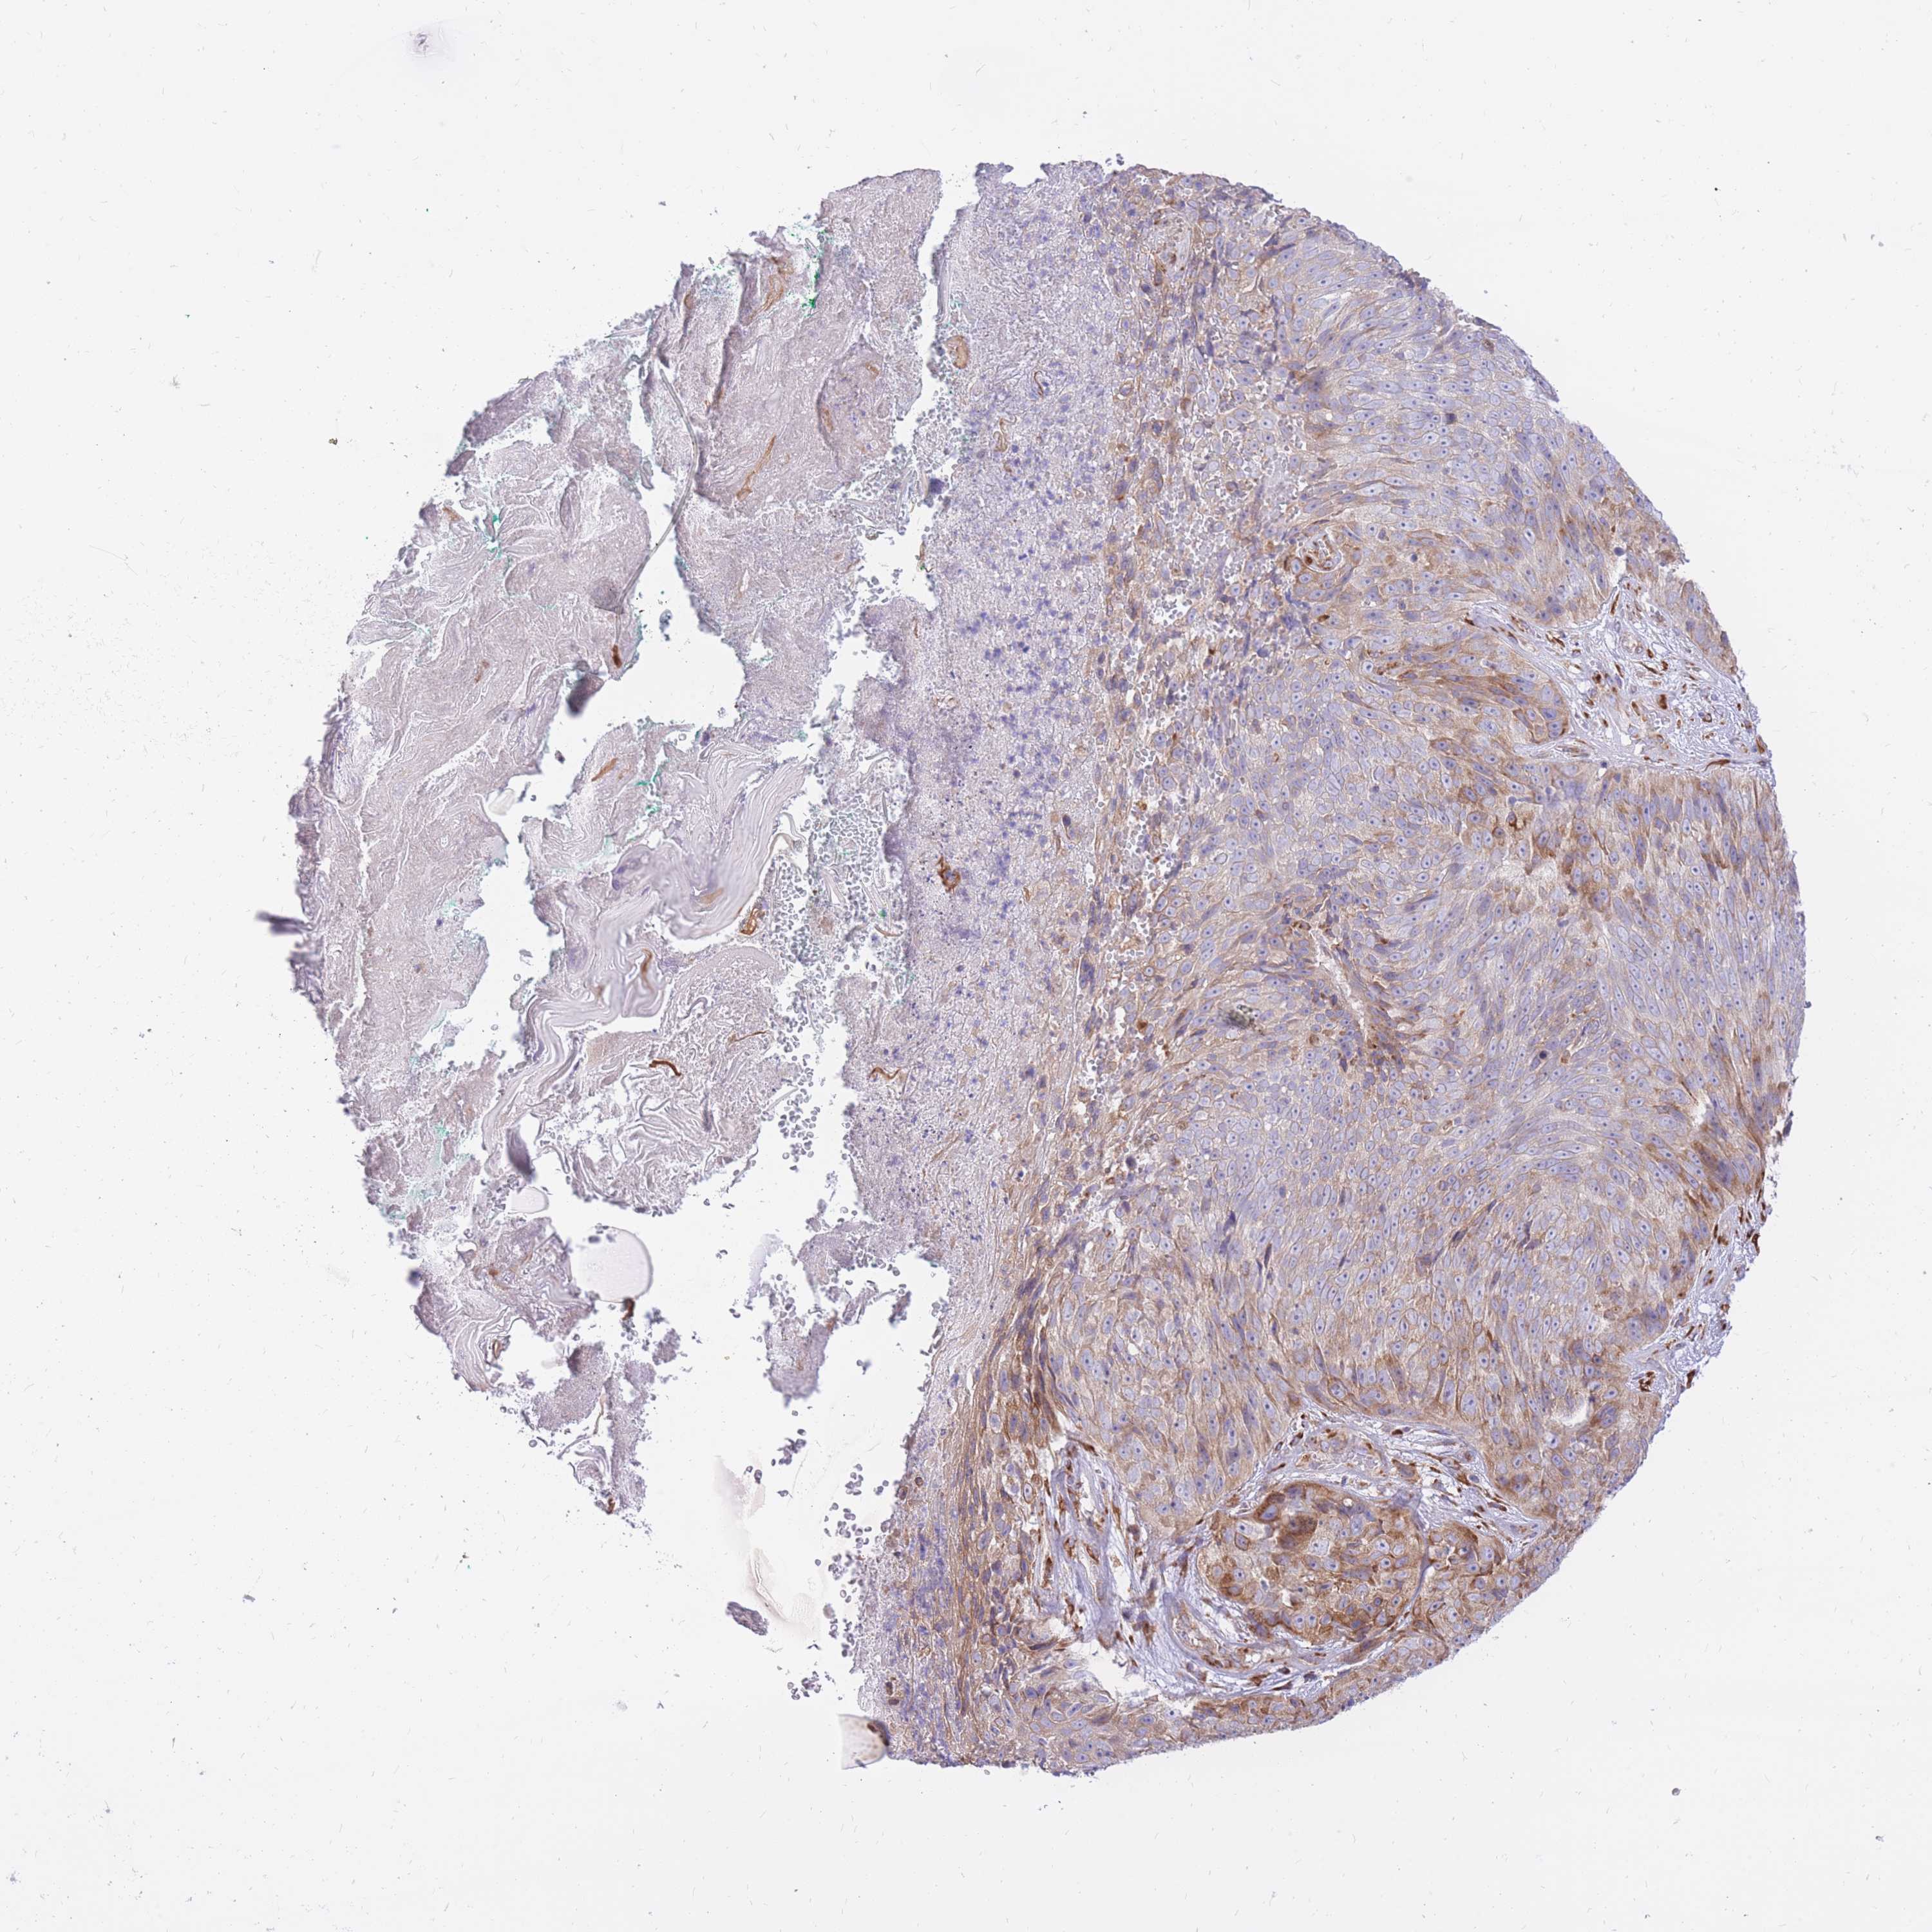

SKIN CANCER - Protein expressioni

A mouse-over function shows sample information and annotation data. Click on an image to view it in a full screen mode. Samples can be filtered based on level of antibody staining by selecting one or several of the following categories: high, medium, low and not detected. The assay and annotation is described here.

Antibody stainingi

Antibody staining in the annotated cell types in the current human tissue is reported as not detected, low, medium, or high, based on conventional immunohistochemistry profiling in selected tissues. This score is based on the combination of the staining intensity and fraction of stained cells.

Each image is clickable and will lead to virtual microscopy that enables deeper exploration of all samples and also displays staining intensity scores, fraction scores and subcellular localization as well as patient and tissue information for each sample.

Antibody HPA051245

Staining

High

Medium

Low

Not detected

Intensity

Strong

Moderate

Weak

Negative

Quantity

>75%

75%-25%

<25%

None

Location

Nuclear

Cytoplasmic/membranous

Cytoplasmic/membranous,nuclear

Basal cell carcinoma

Squamous cell carcinoma, NOS

Squamous cell carcinoma, metastatic, NOS

Squamous cell carcinoma in situ, NOS